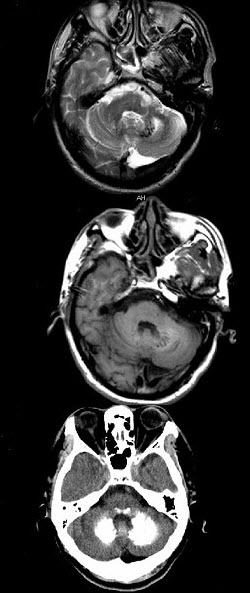

男,49岁,反复发作性癫痫,双手震颤5年,伴头昏行走不稳,生化检查:血清钙降低,血清磷升高,请根据所提供图像,选择最可能的诊断()。

A、Fahr病

B、一氧化碳中毒性脑病

C、霉变甘蔗中毒

D、肝豆状核变性

E、甲旁低

E